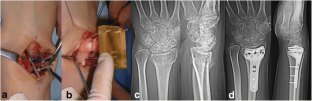

Fig.. 1